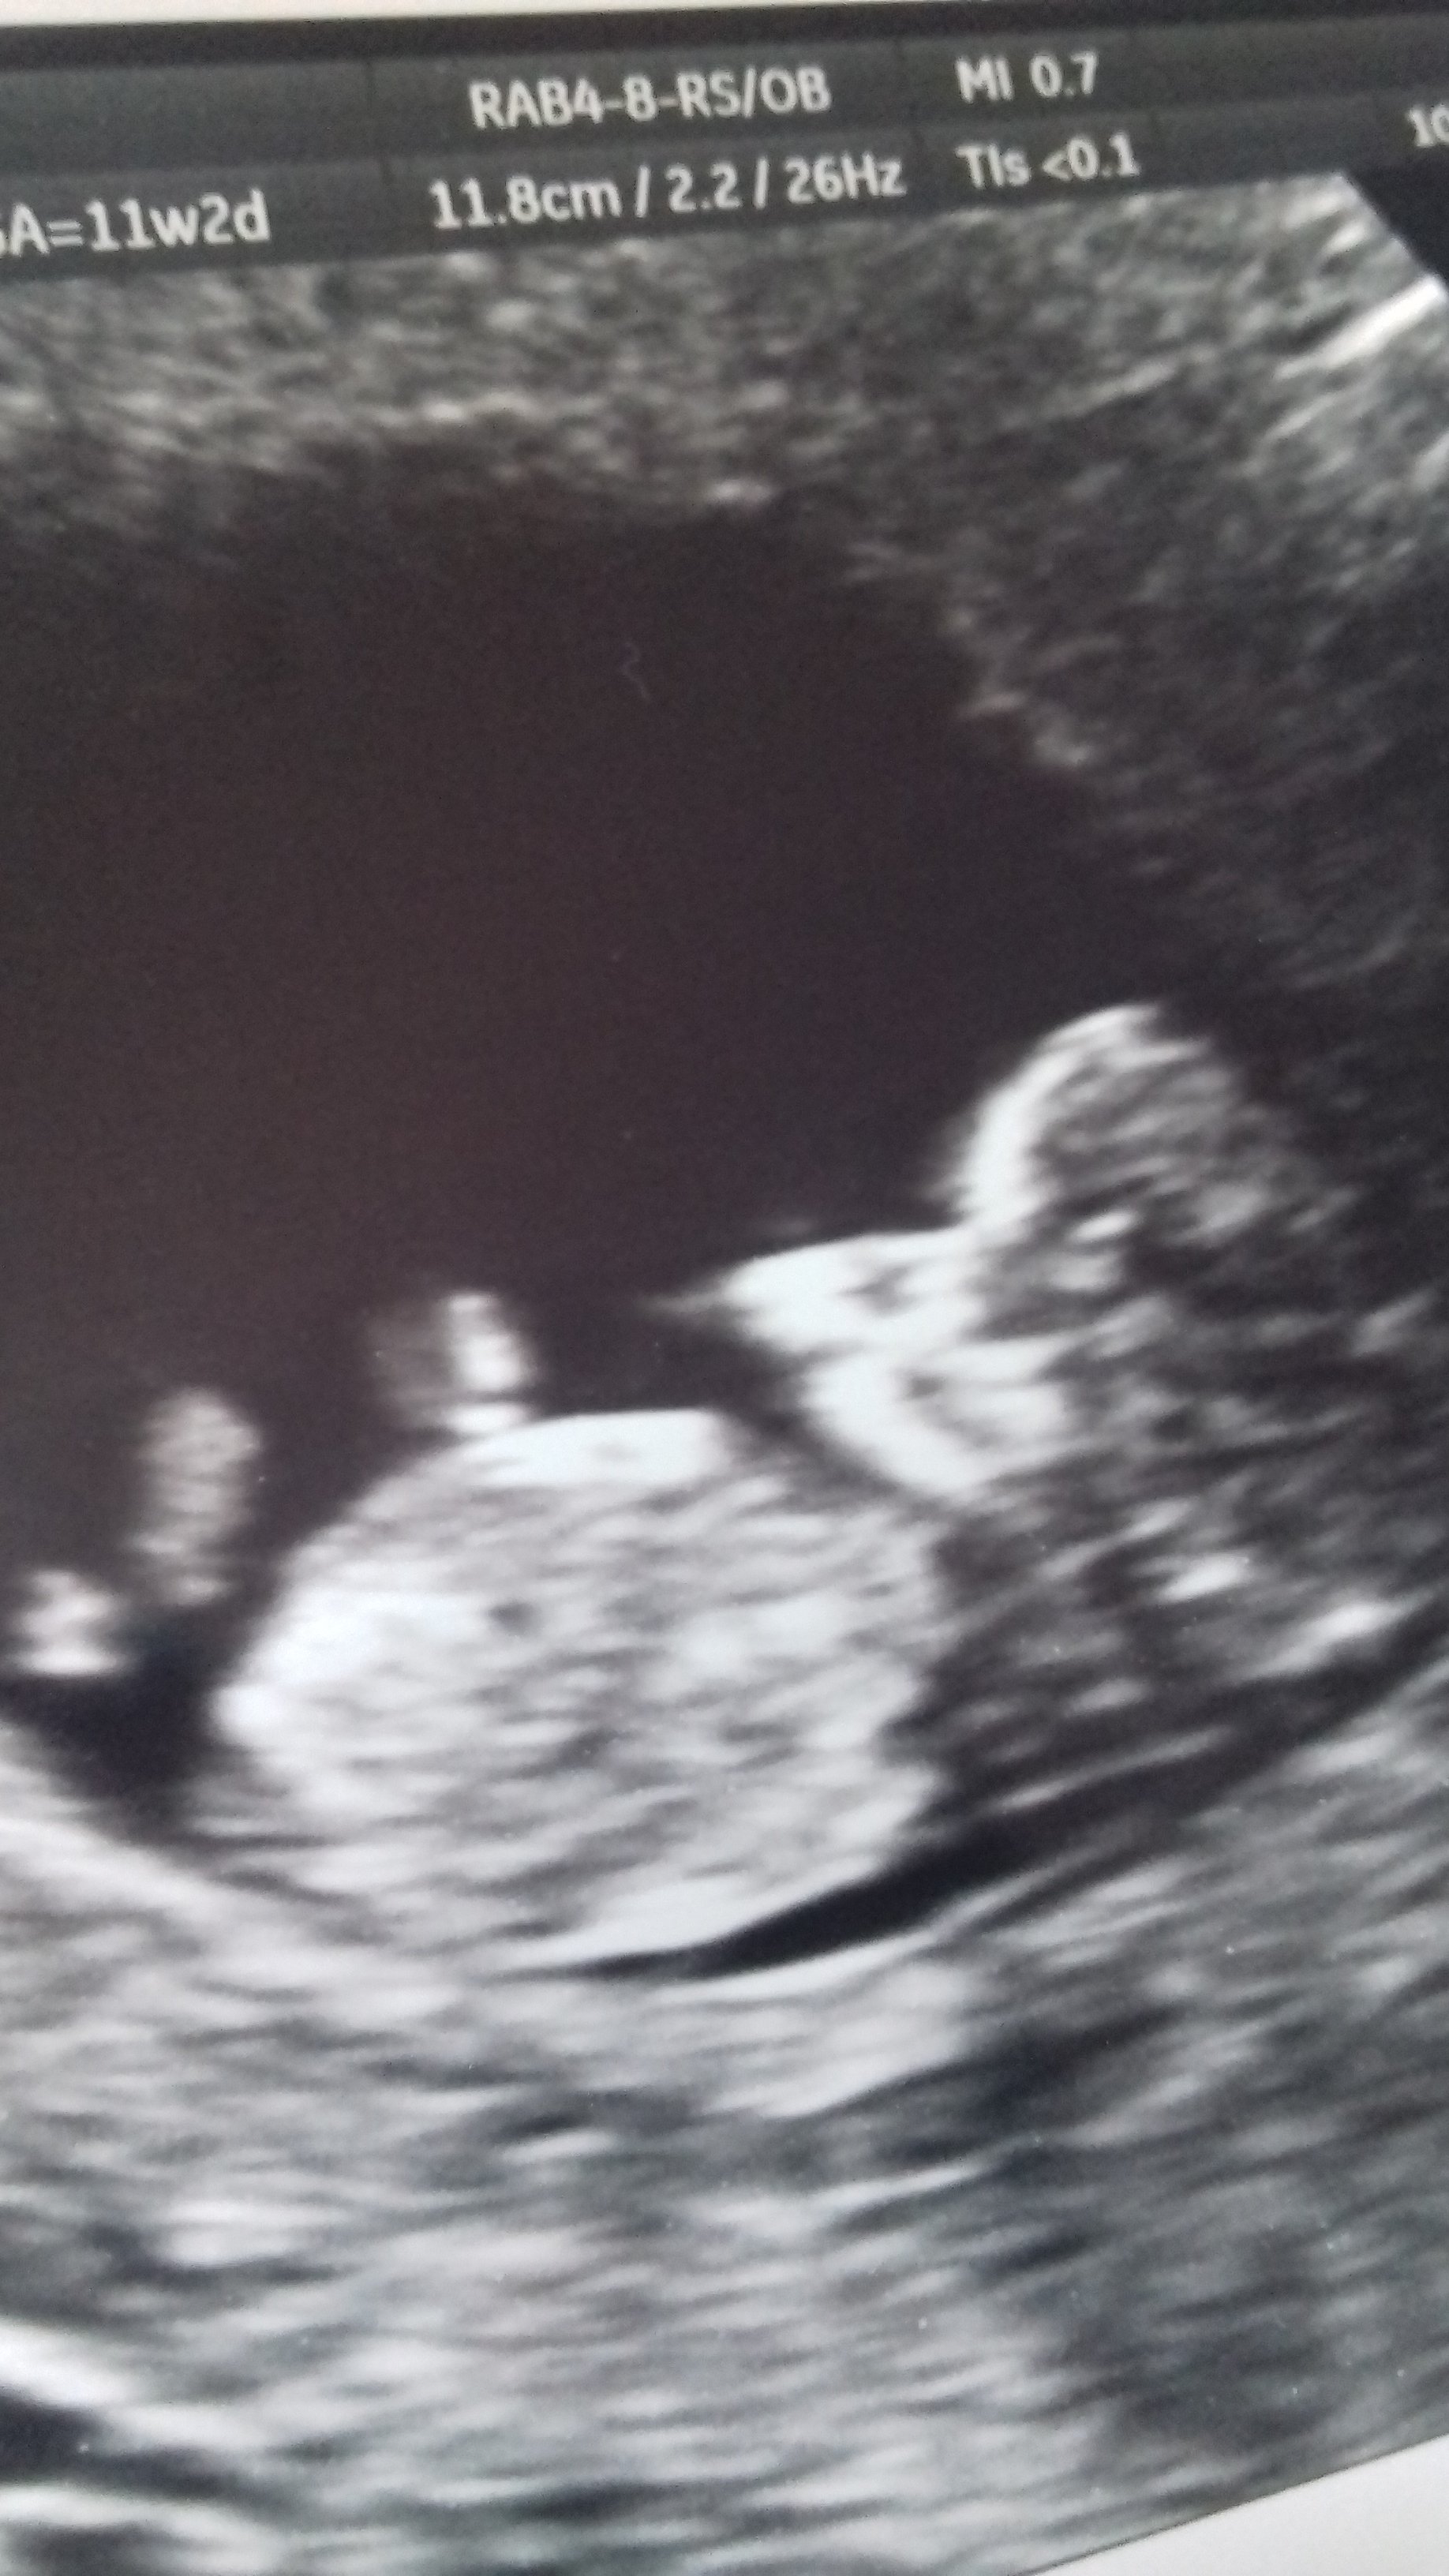

Dziewczyny jestem po wizycie. Dzidzia zdrowa. Mialam zrobione prenetalne i wyniki sa prawidlowe. Ciaza starsza o prawie tydzien i termin porodu 2 marca. Jestem mega szczęśliwa ☺

20170810_181642.jpg

Załączniki

• 20170810_181642.jpg

597,8 KB · Wyświetleń: 725